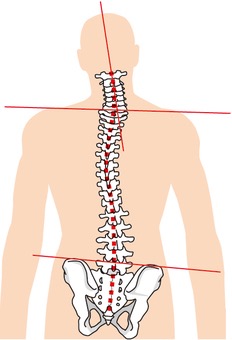

不良姿勢や身体の使い方のクセ

日頃の不良姿勢からくる身体のゆがみや片足重心などのクセがあると、膝に偏った負担がかかります。

膝が痛い=膝だけが悪いとは限らず、股関節や足首、骨盤などの影響を受けているケースも非常に多いです。

Yさんの膝の痛みの原因は身体のゆがみからきていた

問診や検査でYさんのお身体の状態を詳しく検査させていただくと、骨盤に大きなねじれが見られました。

膝に直接関係する、整形外科的テストなどをしても特に異常は見られませんでしたし、膝自体もしっかり曲げ伸ばしできて、可動域にも問題ありませんでした。

そこで、身体のゆがみを整える施術をさせていただくと、膝の痛みは徐々に消失していきました。

膝に負担をかけている身体のゆがみを探し出して、正しい位置に調整していくことが必須になります。